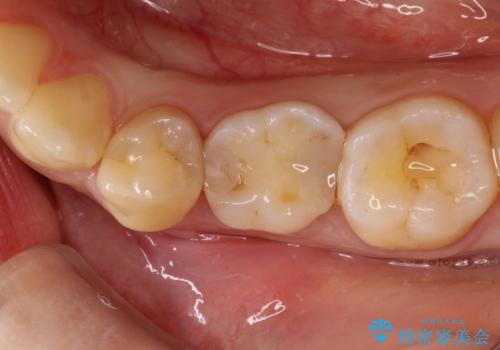

【セラミックインレー】虫歯の治療

- 定期検診にてむし歯を認めたため、セラミックインレーにて修復を行いました。

e-max プレスインレーにて修復治療を行っているため適合性及び審美性の高い治療を行うことができます